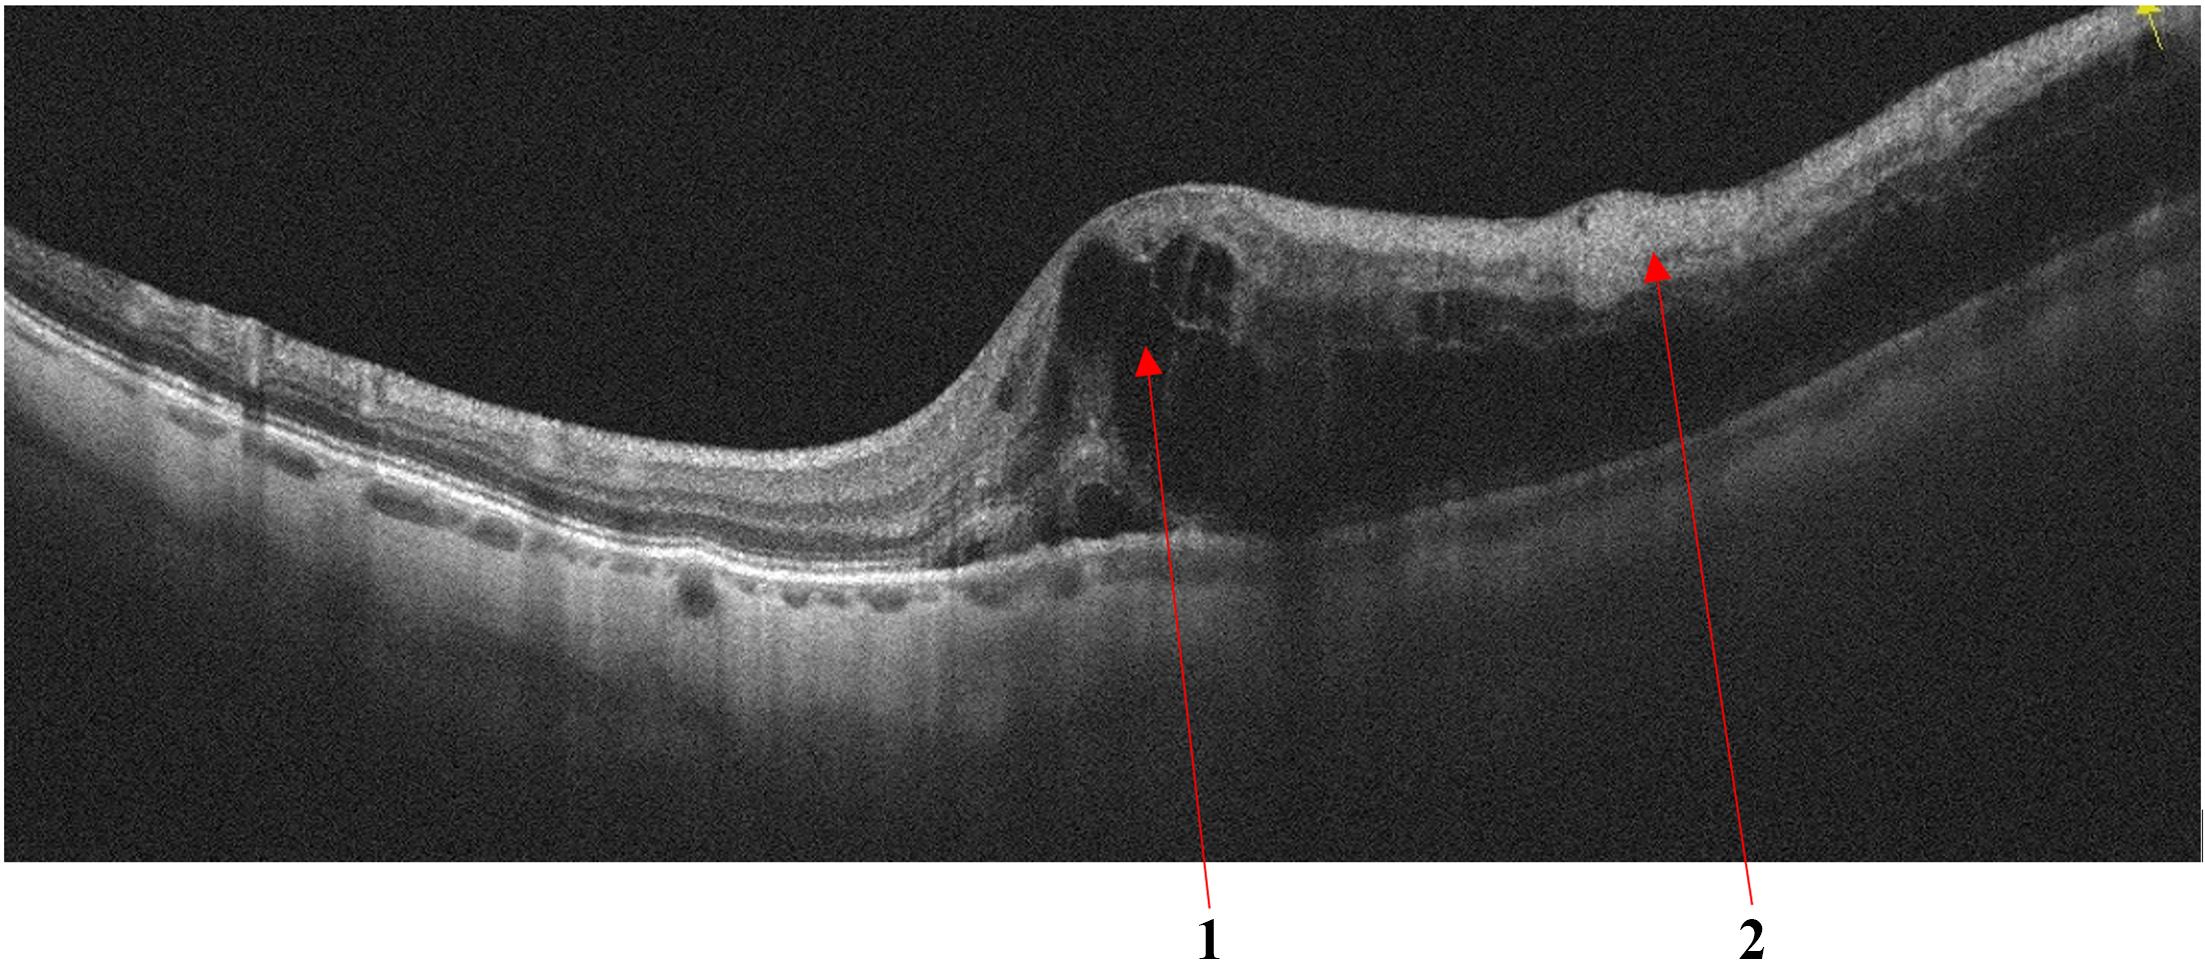

Fig.3 shows examples of AMD: the retinal profile is deformed, and the normal foveal architecture is disrupted. In Fig.3a the inner retinal layers are thinned and contain outer retinal tubulations or cystic spaces, highlighted with number 1. Subfoveolarly, a hyporeflective region is visible beneath the retinal pigment epithelium - in Fig.3a highlighted with number 2. Hyperreflective coloration of the choriocapilaris below the RPE layer atrophy is apparent. Local and diffuse decreases in the thickness of the choriocapillaris layer. Fig.3b shows different fluid-filled spaces in the macular that may accompany the clinical features of AMD:

• Subretinal fluid - space between the RPE and the neurosensory retina, in Fig.2b is shown with number 1.

• Intraretinal fluid, a kind of hyperreflective cyst - a cyst in the inner retina, but the content differs in reflectivity - with a granular appearance indicating the presence of more reflective elements that may be cellular debris or protein that has leaked into the space, in Fig.2b is shown with number 2.

• Sub-retinal pigment epithelial fluid - a hyporeflective space between Bruch’s membrane and the basolateral membrane of the RPE in Fig.2b is shown with number 3. This may be due to the breakdown of fluid regulation by the ion channels of the RPE [31].

Figure 3: Age-related Macular Degeneration (AMD). Markers (a): 1 - outer retinal tubulation or cystic spaces; 2 - Subretinal fibrosis causing distortion of the macular and hyporeflectivity of the underlying choroid. Types of fluid (b): 1 - subretinal fluid; 2 - intraretinal fluid; 3 - sub-retinal pigment epithelial fluid accumulation.